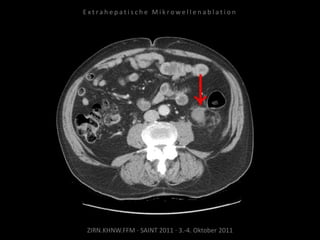

Verlaufskontrolle:

CTs und MRTs

CT vom 08.02.2011

Kein Vitalitätsnachweis.

Resultat:

Erfolgreiche Behandlung des

Tumorrezidivs.

Fazit:

Die MWA ist geeignet, um Tumorgewebe

an kritischer anatomischer Position zu

behandeln.